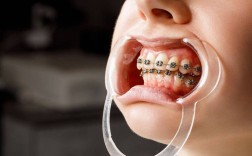

在牙齿矫正技术方面,上海宏康口腔科提供多样化选择,满足不同患者的需求,目前主流的矫正技术包括金属托槽矫正、陶瓷半隐形矫正、隐形无托槽矫正及舌侧隐形矫正等,各类技术特点对比鲜明:金属托槽矫正性价比高,适用复杂错颌畸形,但美观度较低;陶瓷托槽与牙齿颜色相近,兼顾美观与强度,适合对美观有一定要求的患者;隐形矫正采用透明牙套,可自行摘戴,不影响饮食和社交,尤其适合成年及青少年群体;舌侧矫正完全隐藏于牙齿内侧,美观度极高,但对医生技术要求严苛,价格也相对较高,科室会根据患者的牙齿畸形程度、咬合关系、面部美学及个人需求,综合推荐最适合的矫正方式。